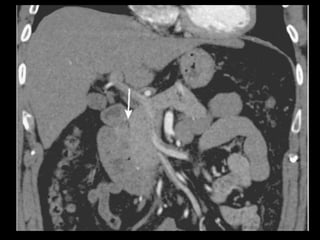

Hemorragia

Geralmente uma consequência tardia, devido a um

vazamento difuso do tecido de granulação

inflamado ou às lesões vasculares produzidas pelas

enzimas pancreáticas ativadas e extravazadas.

Artéria esplênica e seus ramos e artérias das

arcadas pancreaticoduodenais.

TC: líquido com alta atenuação na cavidade

peritoneal ou no retroperitônio, numa coleção

líquida preexistente ou num pseudocisto;

Tratamento: angiografia de emergência, com

embolização seletiva.